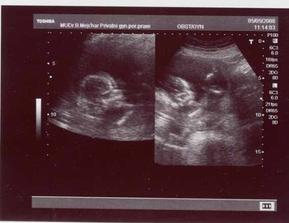

2.4. - podrobný UTZ (screaning v I.trimestru a vše v pořádku hurááá) - mimčo je čiperné, krásně na UTZ skotačí!!!